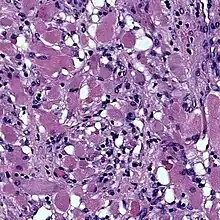

Cardiac rhabdomyomas are the most common primary tumor of the heart in infants and children. It has an association with tuberous sclerosis.[1] In those with tuberous sclerosis, the tumor may regress and disappear completely, or remain consistent in size.[2] A common histological feature is the presence of spider cells, which are cardiac myocytes with enlarged glycogen vacuoles separated by eosinophilic strands, resembling the legs of a spider.

Photomicrograph of fetal-type rhabdomyoma: Note the plump, pink benign skeletal muscle cells.